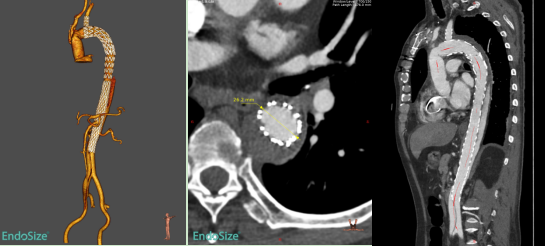

术前CTA

本次入组患者为60岁男性,1个多月前因急性Stanford A型主动脉夹层在我院接受“主动脉瓣交界悬吊+升主动脉及全弓置换+降主动脉象鼻支架置入+三尖瓣成形术”。术后1个月复查CTA提示:象鼻支架以远残余夹层,且夹层累及胸降主动脉、腹主动脉、右侧髂总及髂外动脉,真腔狭窄,假腔大,胸腹主动脉多发夹层破口,胸段肋间动脉以假腔供血为主。